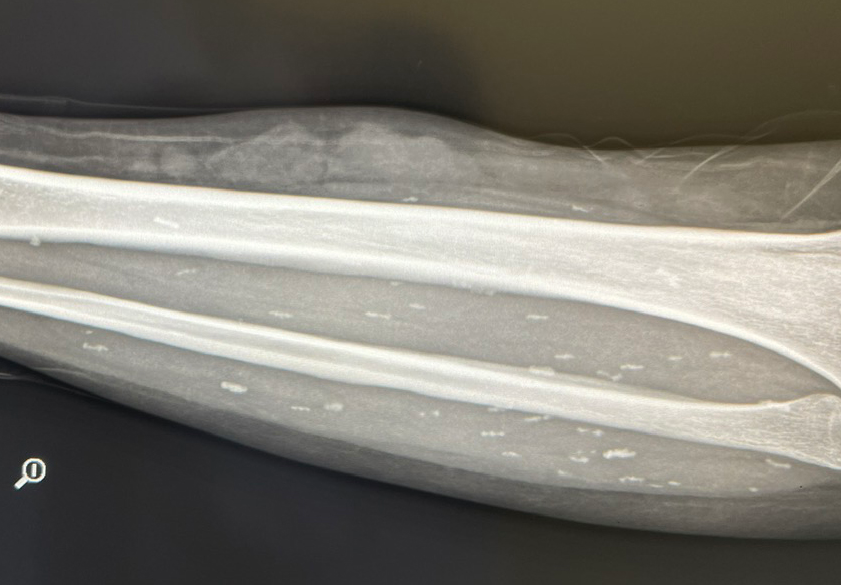

Khi ông vào Trung tâm Y tế Thanh Sơn (Phú Thọ), kết quả CT ổ bụng cho thấy hình ảnh giãn đài bể thận niệu quản phải do sỏi niệu quản 1/3 giữa, sỏi thận hai bên, sỏi túi mật, thoát vị bẹn phải. Đặc biệt, bác sĩ phát hiện "vật thể lạ" là những ấu trùng sán rải rác khắp cơ thể, đường kính 3-5mm.

Theo bệnh nhân, ông thường xuyên ăn đồ tươi sống, chưa chín như gỏi cá, tiết canh, nem chạo, thịt tái, thịt ủ chua…